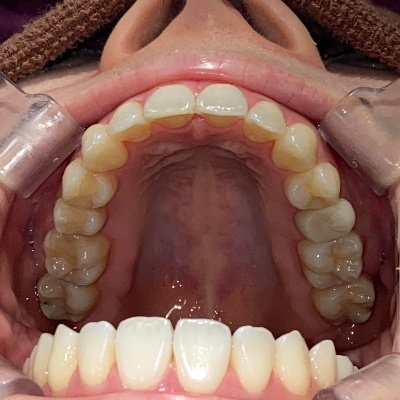

上下前歯の歯並びがガタガタしているのが気になる、きれいにしたいとのご希望で来院されました。

来院時の歯並び写真